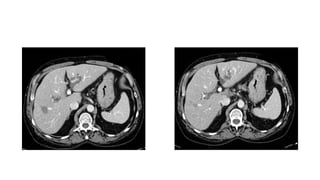

Caso Cerrado 21

Abril Ana Casas

Historia • Varón de 50

años con historia de hepatitis crónica e hipertensión portal